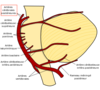

Le support vasculaire artériel des hémisphères cérébraux est assuré par quoi? (2)

- Circulation antérieure

- Artère cérébrale antérieure (ACA)

- Artère cérébrale moyenne (ACM)

- Circulation postérieure

- Artère cérébrale postérieure (PCA)

La circulation antérieure provient de quelles artères?

des artères carotides internes

La circulation postérieure provient de quelles artères?

provient des artères vertébrales

La cirbulation antérieure et postérieure sont unis par quoi?

le polygone de Willis.

Nommez les branches de l’artère carotide interne

OPAAM

- O: Artère ophtalmique

- Passe par le canal optique avec le nerf optique.

- Vascularisation de la rétine.

- P: Artère communicante postérieure

- A: Artère choroïdienne antérieure

- A: Artère cérébrale antérieure

- M: Artère cérébrale moyenne

Nommez les artères constituant le polygone

- Artères cérébrales antérieures

- Artère communicante antérieure (anastomose entre les deux ACA)

- Artères cérébrales moyennes

- Artères communicantes postérieures (anastomose entre l’artère carotide interne et l’artère cérébrale postérieure)

- Artères cérébrales postérieures